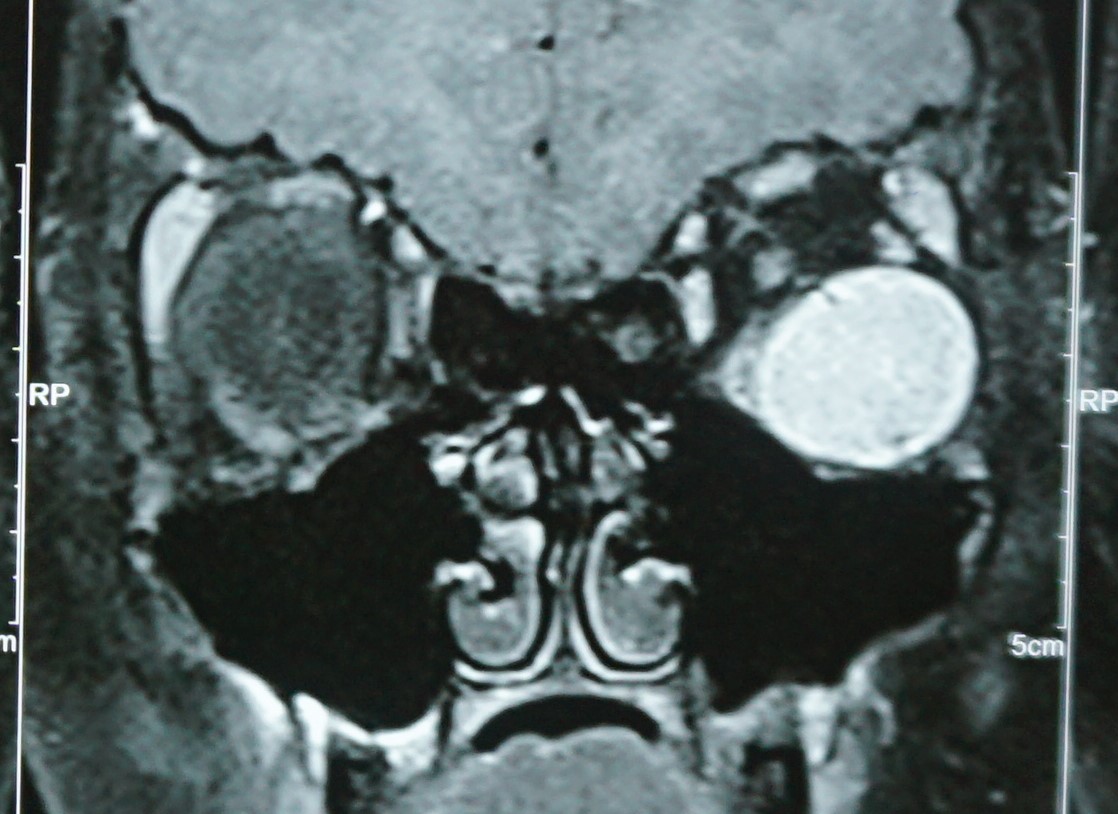

ORBITAL SURGERY

• Tumors